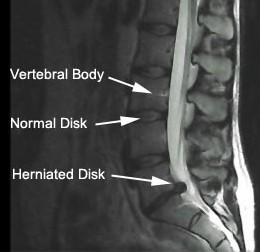

A herniated disc in the lower back can press on the sciatic nerve and cause sciatica. A herniation (or bulge) is when a disc protrudes out from between the vertebrae. Herniations can be caused by an accident or, more commonly, by months or years of uneven pressure due to muscle imbalances.

You can see in this MRI (to the left), the disc bulging out to the right and pressing on the nerve. This is what can happen when a

muscle imbalance

is not corrected.